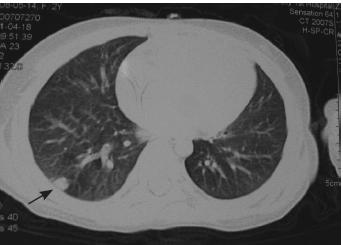

毛霉菌感染常可侵袭多脏器,故行全身影像学检

查。头颅及腹部CT 扫描未见异常,肺部CT 平扫

示右肺下叶胸膜下区见一结节样高密度影,大小

约0.7 cm×0.5 cm(图2),符合肺部毛霉菌感染

的影像学改变。结合患儿强力抗细菌治疗无好转

且继续进展及病理改变,临床确诊为毛霉菌感染。

治疗2 周后复查肺部CT 示高密度影较前吸

收,3 周后除颜面残余一处皮肤包块外,其余均消

退,共用药 4 周。停药 1 个月后,再次复查肺部

CT 示病灶已吸收。